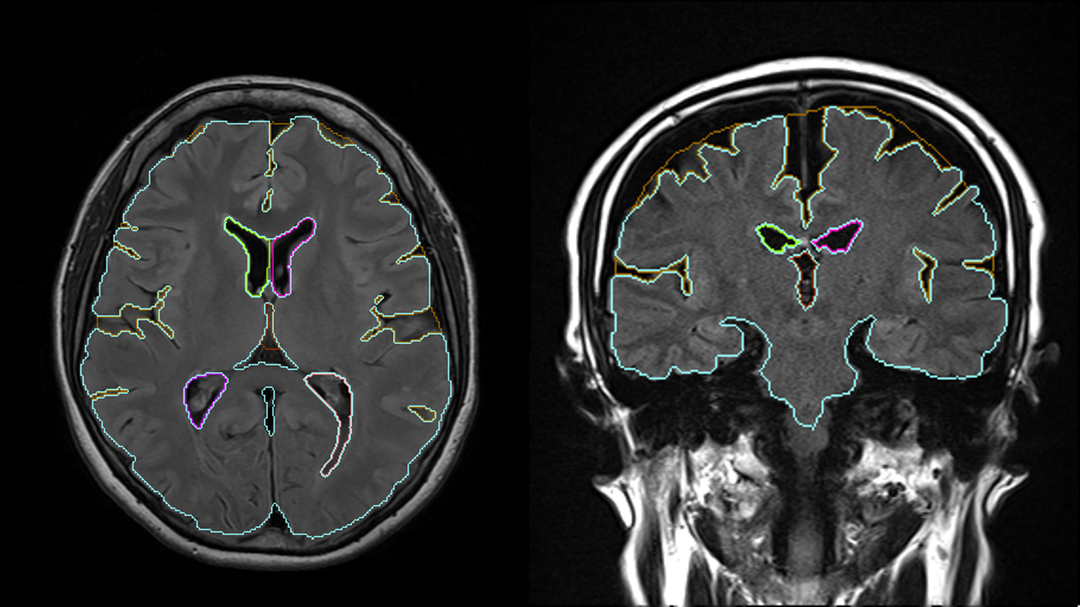

AIが認知症リスク因子を定量化

認知機能低下の要因となる脳萎縮や白質病変、全脳505構造を解析。人間の目では評価が難しい微細な変化も定量化します。

3D T1、2D T1、2D FLAIRに対応。普段通りの撮影フローで運用でき、検査時間の延長はありません。